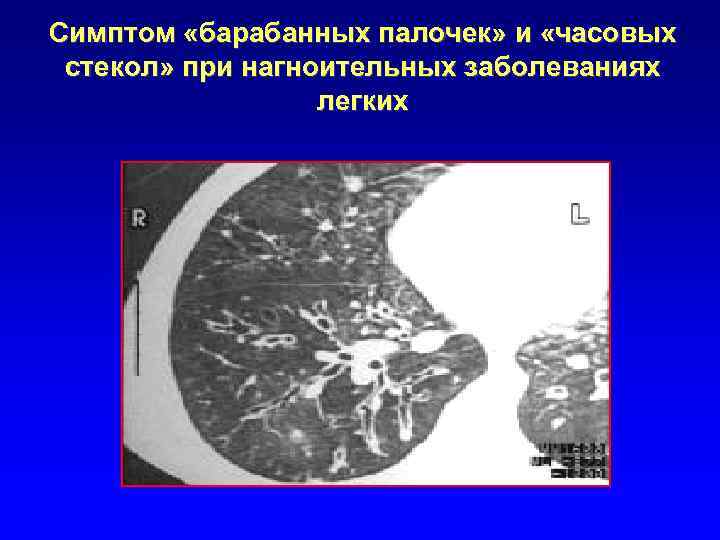

Симптом «барабанных палочек» и «часовых стекол» при нагноительных заболеваниях легких

Компьютерная томография Один из высокоспецифических признаков – бронходилатация: внутренний диаметр бронха больше диаметра сопровождающей одноименной артерии; периферические бронхи прослеживаются в 1 см от поверхности костальной или медиастинальной плевры.